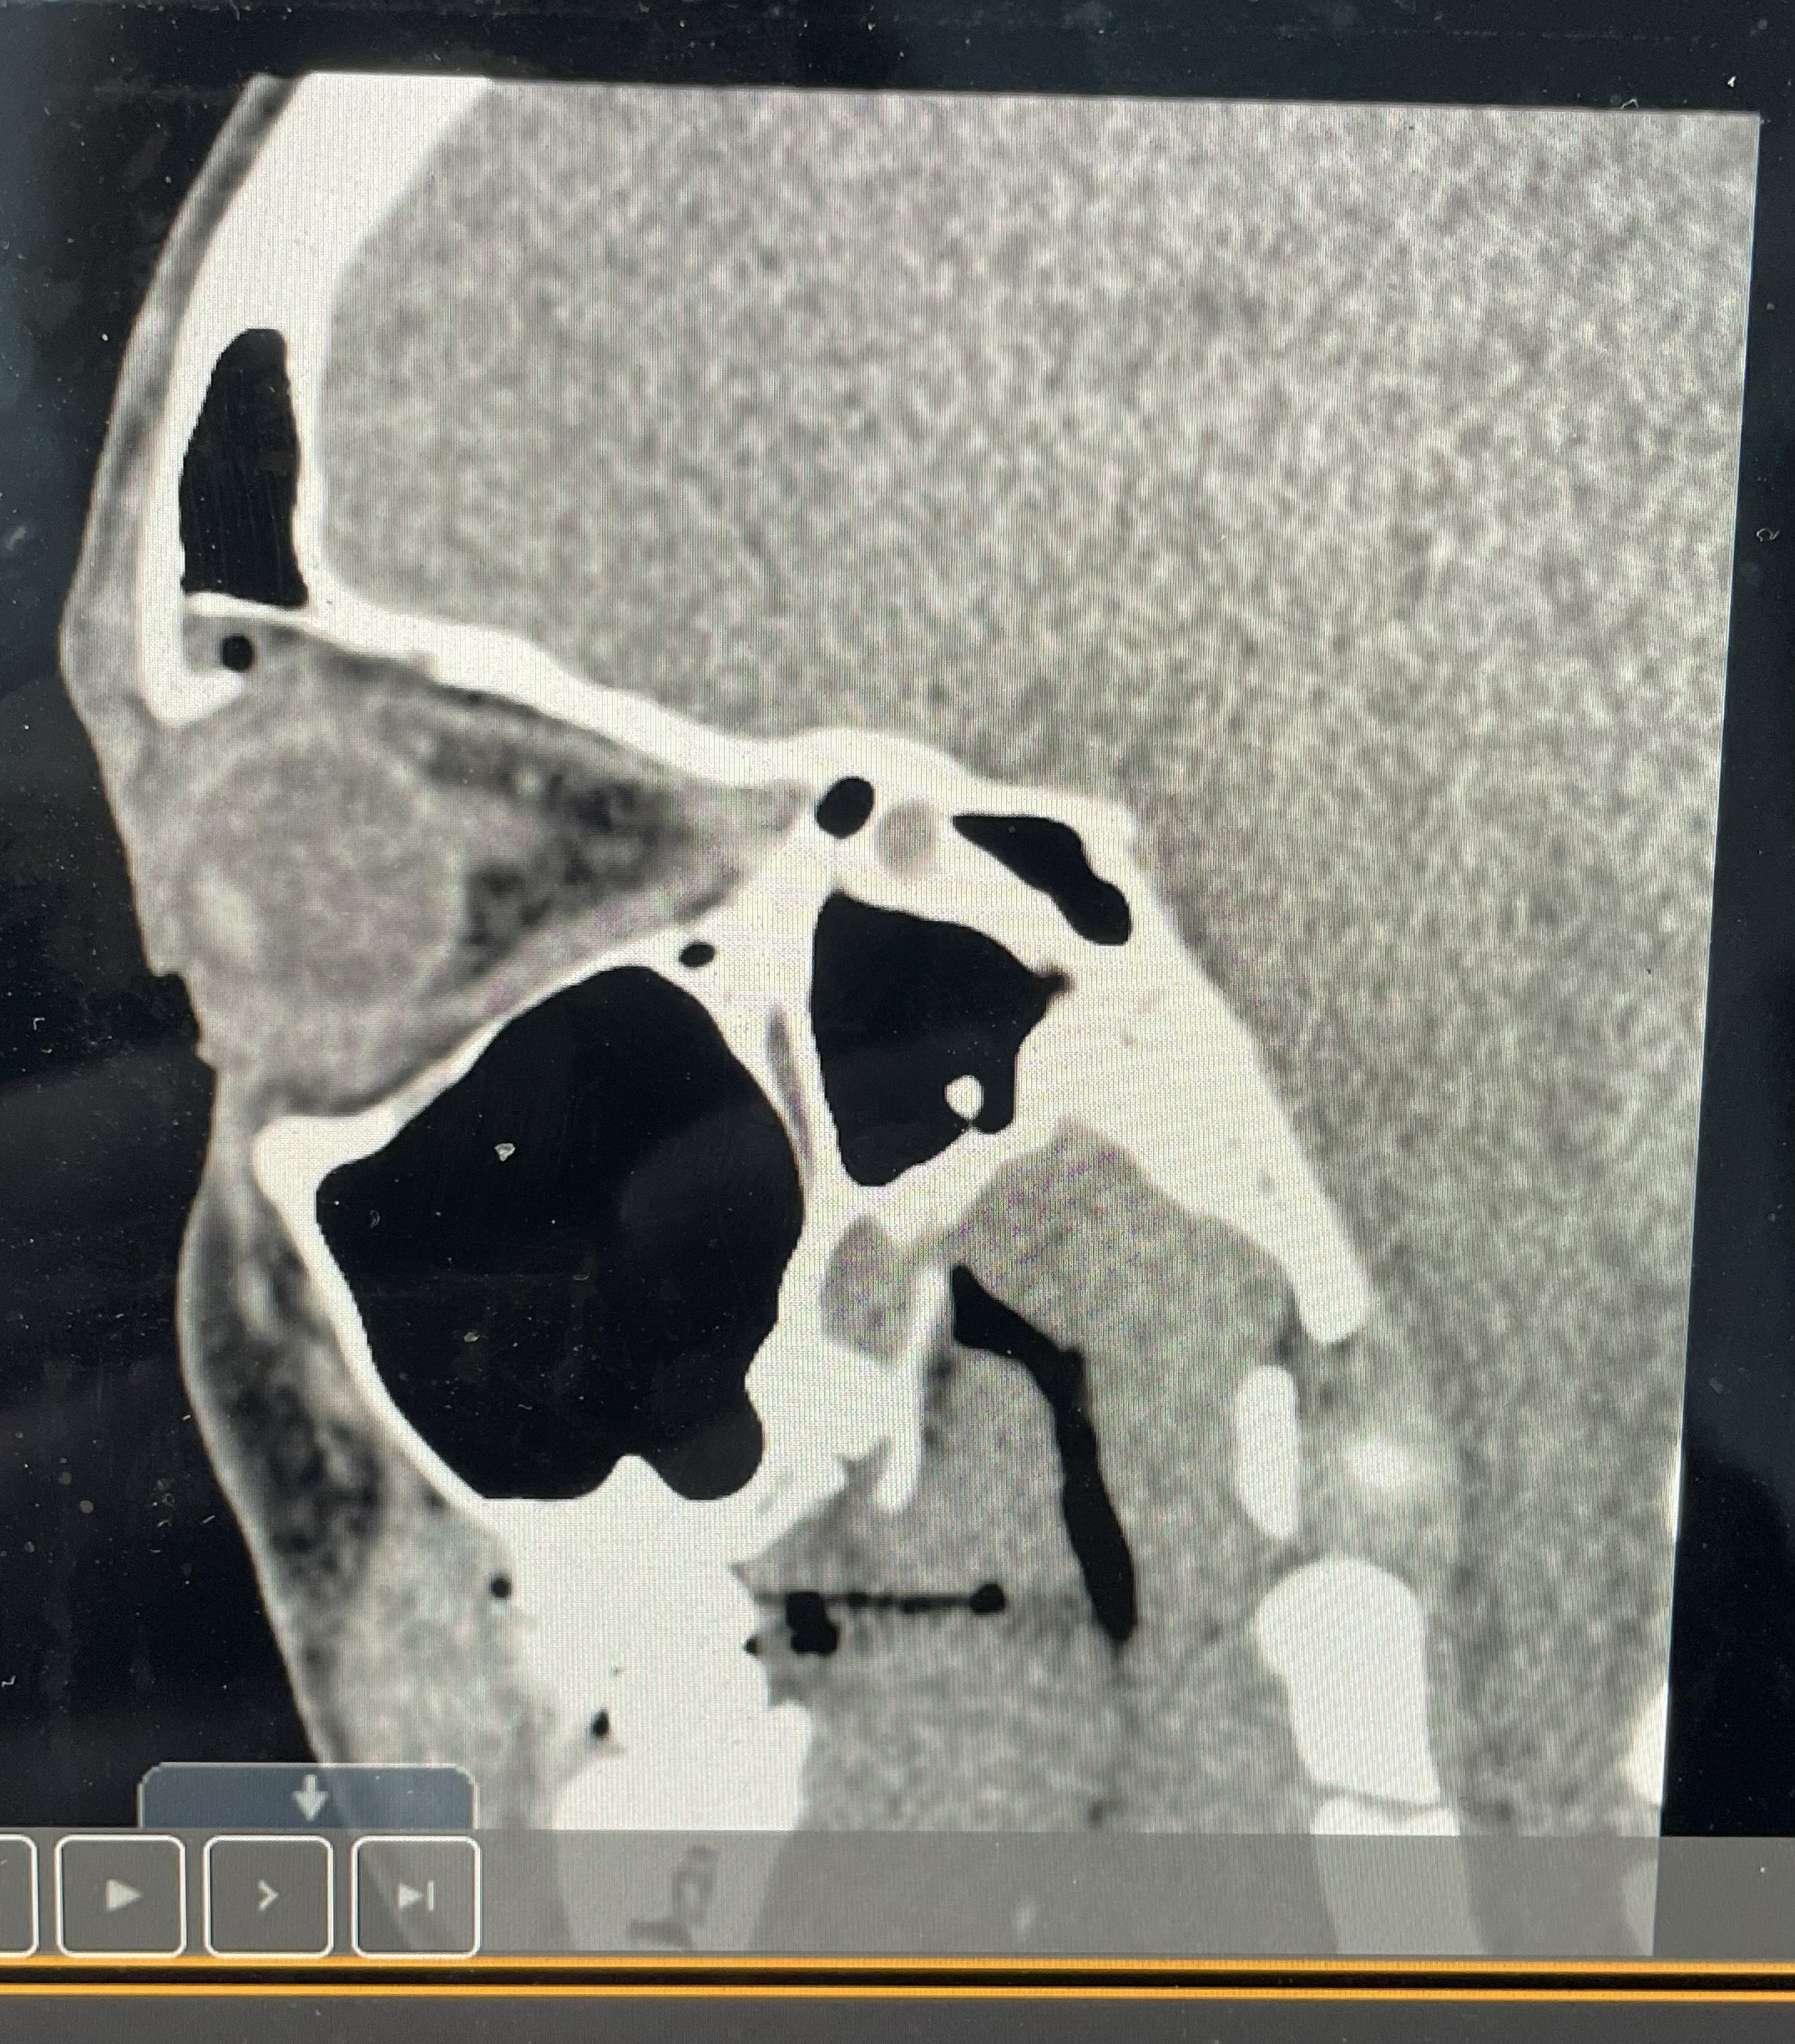

Following the brutal attack, it has been revealed that The Nightmare has suffered a fractured right orbital socket, which will put Ripley out of action for an undisclosed amount of time.

“[Rhea has] got a fractured orbital bone,” Dave Meltzer said on “Wrestling Observer Radio” recently. “So the injury they announced is pretty much legit. It happened last week…Probably the last TV thing because she didn’t work any house shows.”